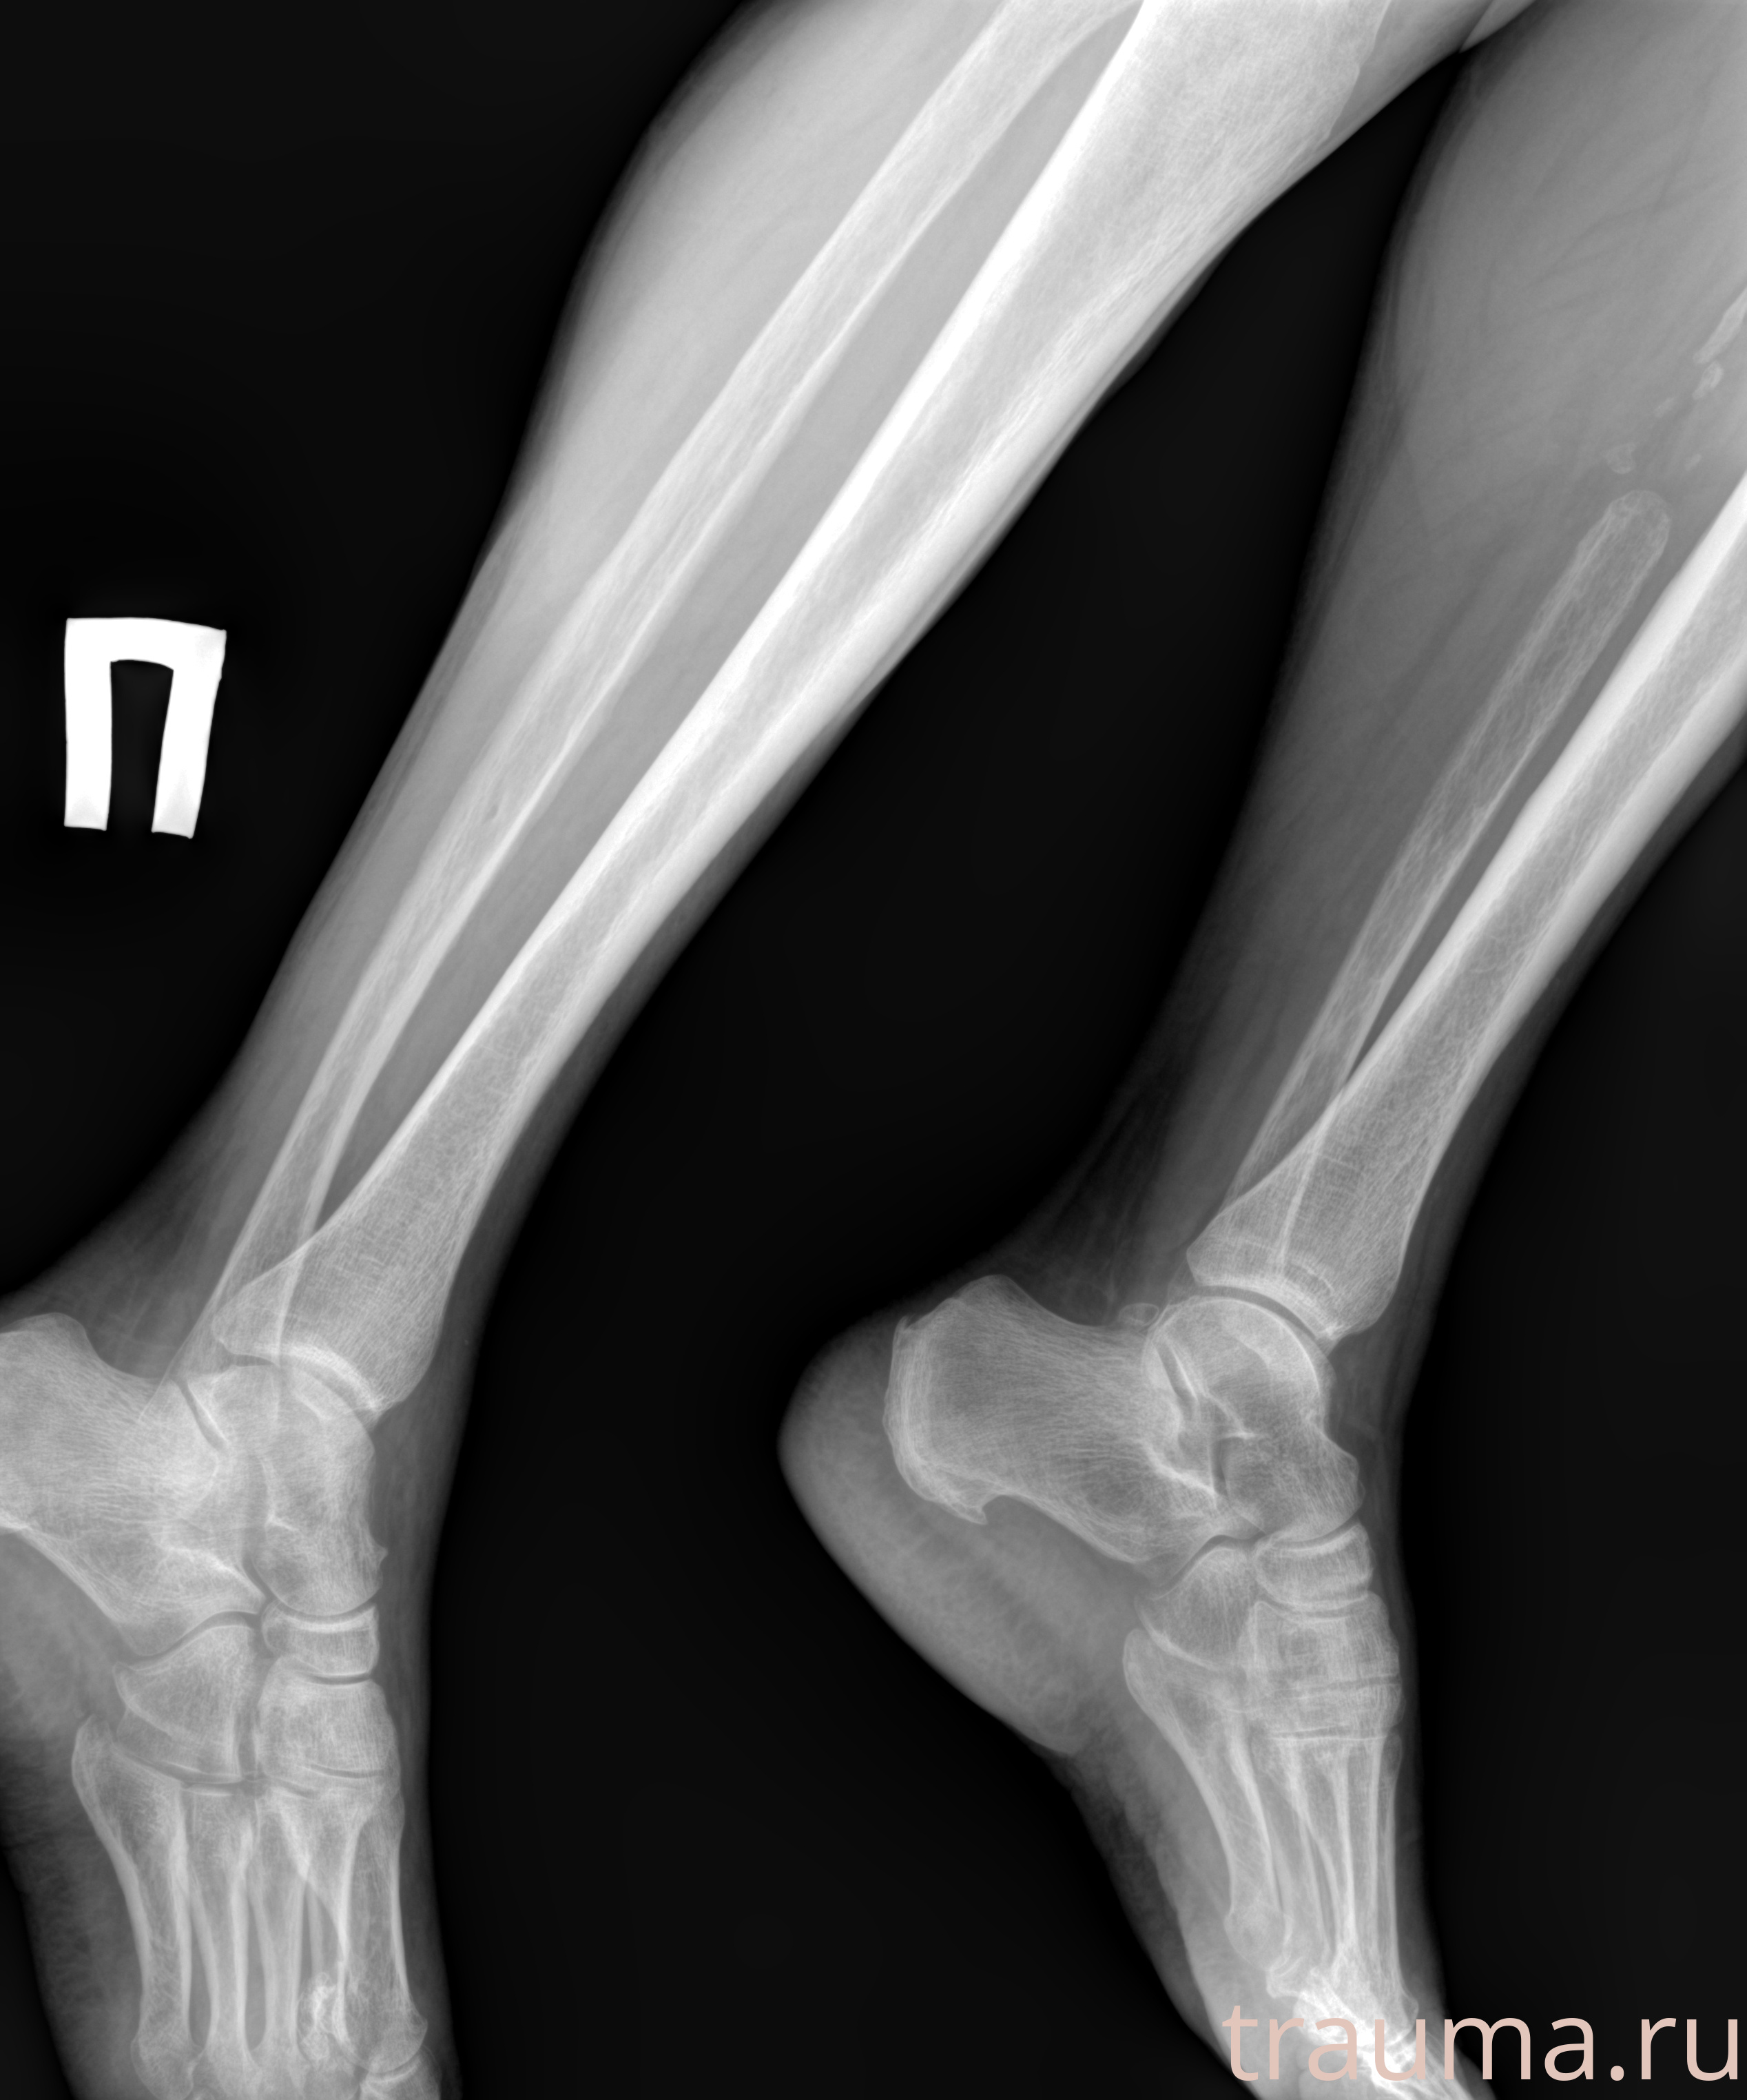

Рентген на дому: по вашему адресу приезжает врач-рентгенолог, травматолог-ортопед с мобильным рентгеновским аппаратом, проводит диагностику травмы или заболевания, делает необходимые рентгенограммы, дает рекомендации по дальнейшему лечению. Получить качественные снимки в домашних условиях возможно благодаря уникальной методике, разработанной МосРентген Центром для института  Склифосовского